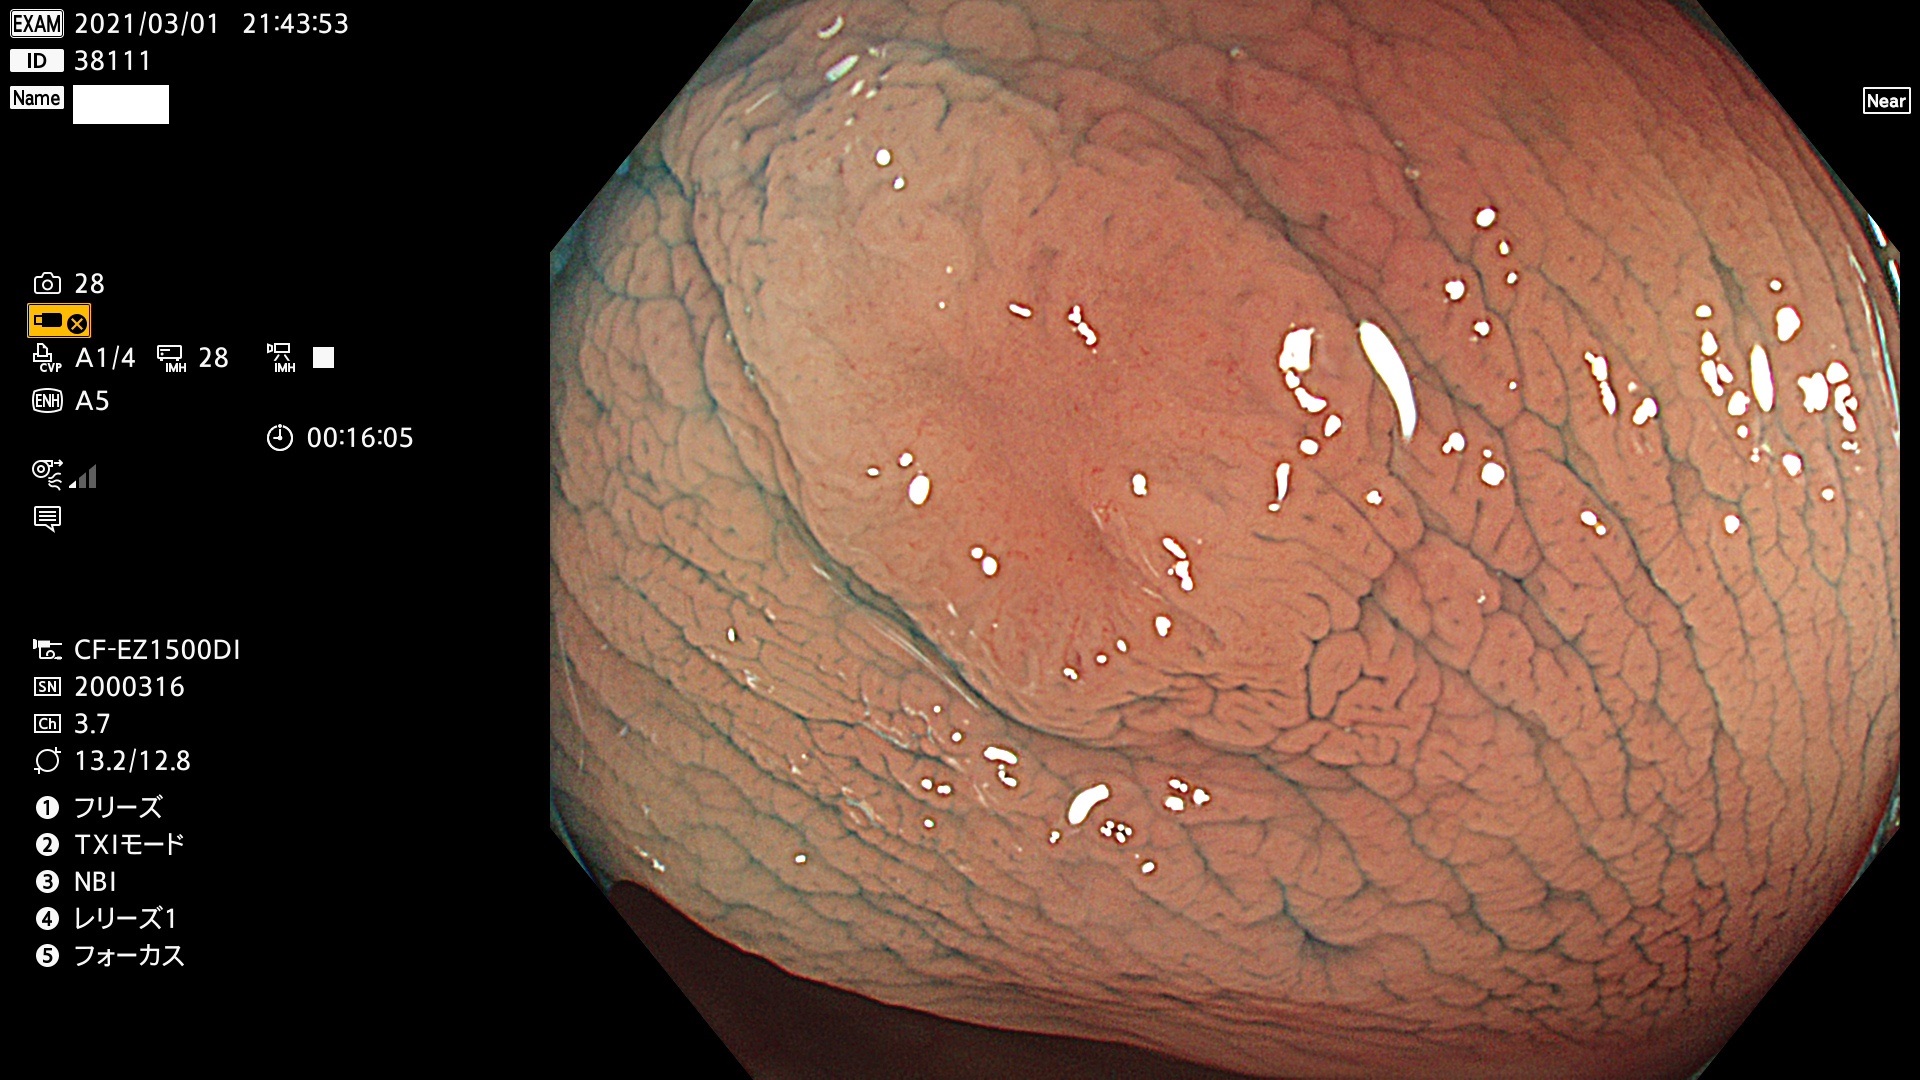

腺腫発見率 72 % (カルテ番号 38100〜38199の100名の方の検査結果で集計)大腸癌検診最新情報

以下のカルテ番号の方に腺腫(Adenoma,Group3〜5)が見つかりました(集計法)

38101 38103 38104 38106 38107 38108 38109 38110 38111 38112 38113 38114 38115 38117 38118 38122 38123 38124 38125 38126 38127 38128 38130 38131 38132 38135 38137 38138 38140 38141 38142(SSAPのみ) 38143 38144 38145 38146 38147 38148 38149 38150 38151 38152 38153 38154 38157 38158 38160 38161 38162 38164 38165 38166 38167 38168 38169 38172 38176 38177 38178 38181 38182 38183 38184 38187 38189 38190 38191 38192 38193 38194 38195 38196(SSAPのみ) 38198

発見困難で危険性の高い平坦型病変(上記100名より抽出) ![]()